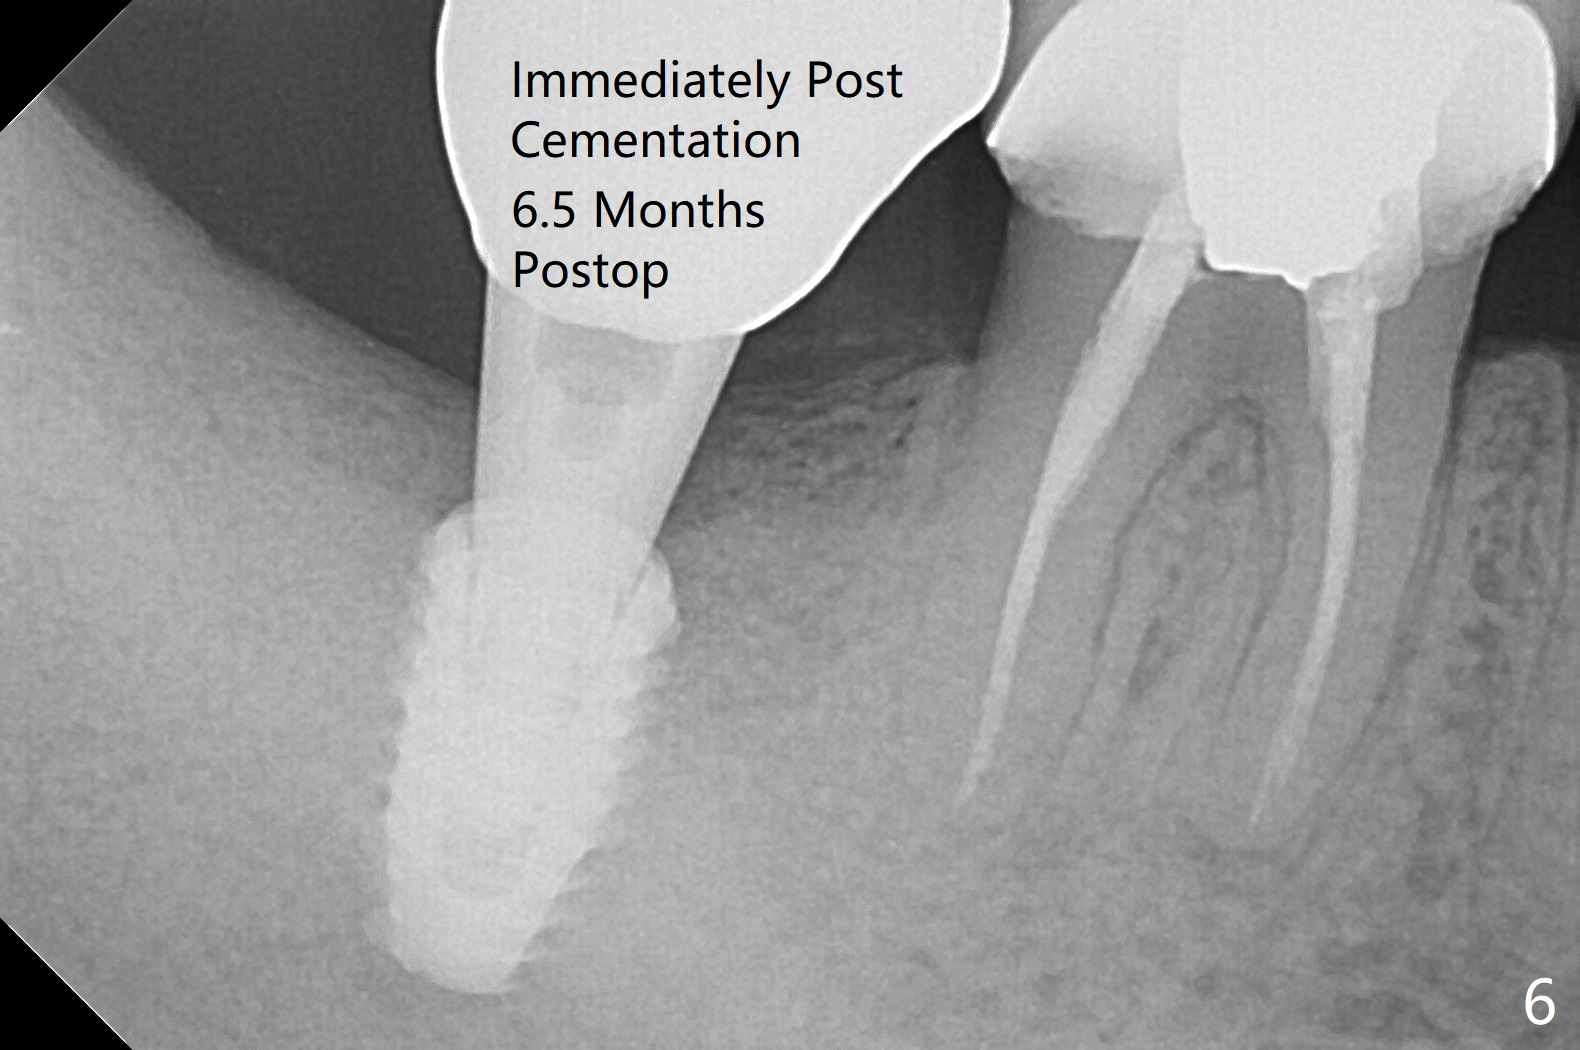

The implant, apparently having been osteointegrated 5.5 months postop (Fig.3), was placed deep, probably related to pressing the distal end of the guide too heavily.  It is difficult to take impression with use of a 5.2x5.5(5) mm abutment.  The access hole is distolingual (Fig.4).  The abutment screw has increased chance of loosening.  Cross bite at #31 is related to the lingualized access hole (Fig.5,7).  It is essential to check the occlusion clinically and in the lab prior to guide design.  Immediately post cementation PA confirms the implant distal placement (Fig.6).

The trajectory is not right, since no matter how the sensors are placed, the implant threads cannot be shown clearly (Fig.10), in consistence with the distolingual access hole (Fig.11).